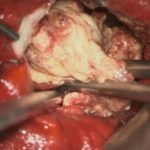

術中写真

摘出 中